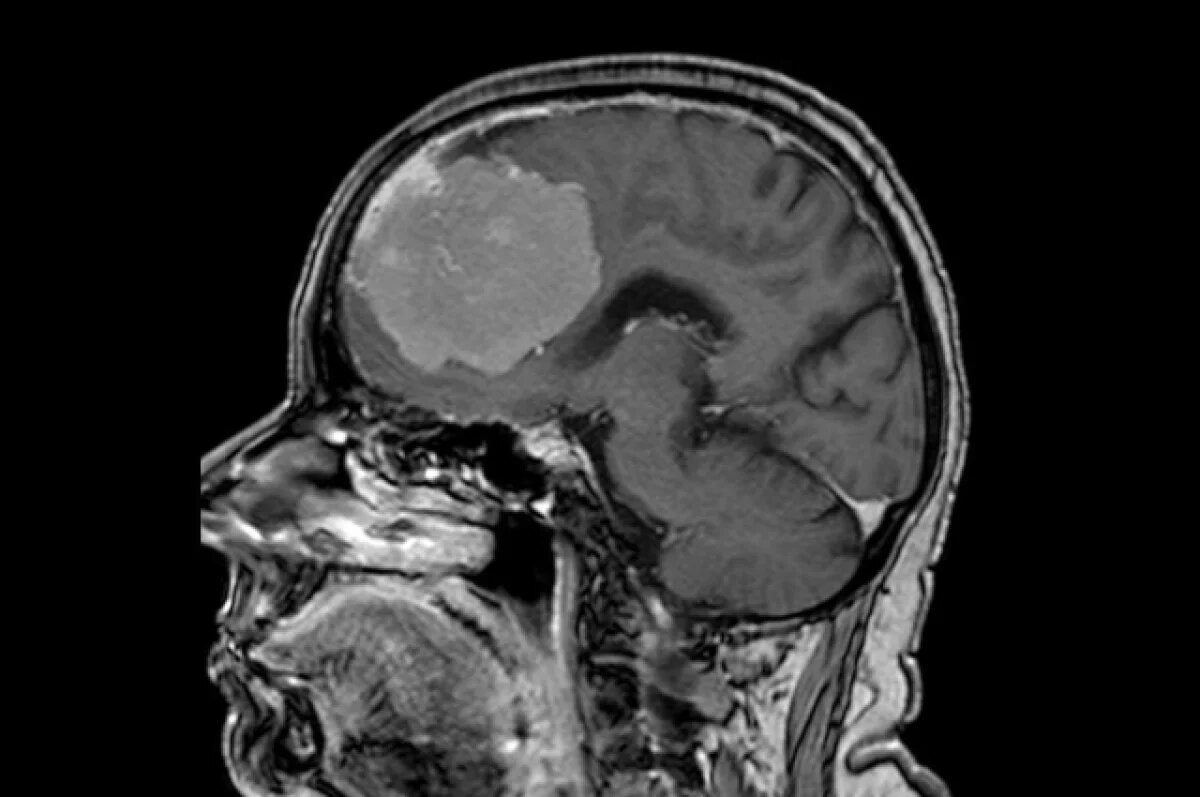

Нейрохирурги БСМП №1 в Воронеже провели сложную операцию по удалению опухоли из головного мозга 80-летней пациентки. Новообразование было размером с грейпфрут, сообщили в региональном министерстве здравоохранения в среду, 21 мая.

В больницу женщина попала с подозрением на инсульт. У пациентки была нарушена речь, а также наблюдалась слабость в правой руке. Обследование с помощью компьютерной томографии не подтвердило предполагаемый диагноз, однако оно показало опухоль в обеих лобных долях мозга.

Врачи отмечают, что подобные новообразования так или иначе затрагивают важные участки мозга – кровеносные сосуды и зоны, отвечающие за речь и движение.

В задачи нейрохирургов входило не только удаление опухоли, но и сохранение здоровья пациентки. Операция длилась шесть часов – врачи удаляли опухоль миллиметр за миллиметром и смогли сохранить все важные сосуды.